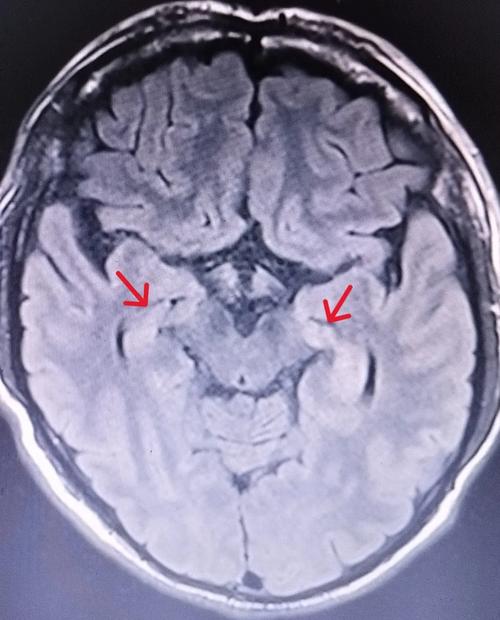

(图片来源网络,侵删)- 常规CT/MRI是首选: 在脑梗塞发生的最初几小时内,头颅CT可能完全正常,而弥散加权成像是MRI序列中最早、最敏感发现脑梗塞病灶的检查,通常在梗塞后30分钟内就能显示出异常,诊断急性脑梗塞,首选是头颅CT和MRI。

- 梗塞灶的显示: 梗塞灶在CT和MRI上会变得非常清晰(表现为低密度信号),PET-CT也能显示梗塞灶,但其主要价值不在于此。